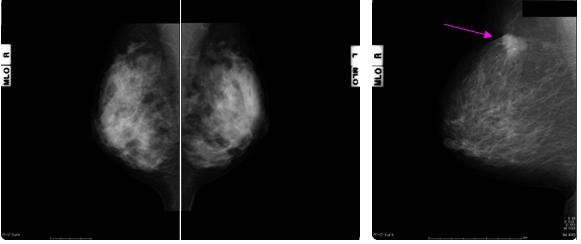

マンモグラフィ(正常例)                マンモグラフィ(右乳がん